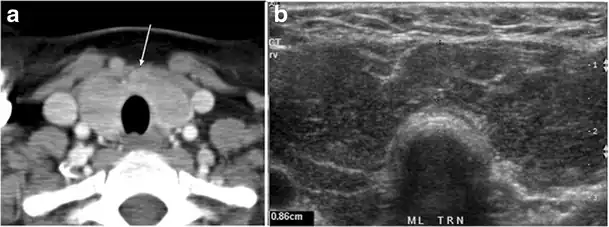

Fig. 14. A 19-year-old male patient known to have multi-nodular goiter and FNA, showing underlying Hashimoto's thyroiditis. a, b Sagittal and transverse greyscale and colour Doppler ultrasound of the neck demonstrate a hypoechoic enlarged right thyroid lobe with small hyperechoic regenerative nodules and marked hypervascularity (white arrows). c, d Enhanced axial CT scan images of the neck demonstrate a heterogeneously enhancing and enlarged thyroid gland, left more than right lobe, and the trachea is markedly narrowed.[1] -